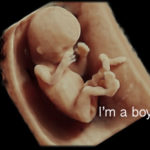

Ultrasound for Gender (15 weeks & up}